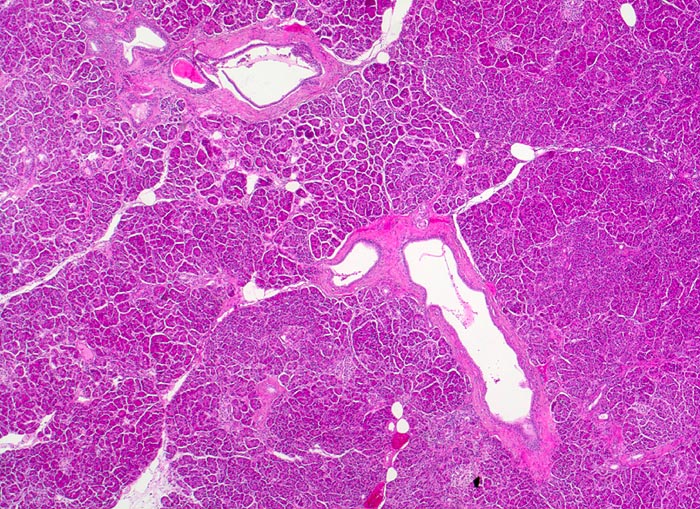

Die meisten Pankreaskarzinome sind mässig bis hoch differenziert und führen zu einer deutlichen desmoplastischen Stromareaktion (derbe Konsistenz). Hochdifferenzierte Tumoren (> 1502) können sehr ähnlich aussehen wie eine chronische Pankreatitis (> 4243). Im Gegensatz zur Pankreatitis sind die neoplastischen Drüsen verformt oder rupturiert und zeigen zelluläre Atypien (grosse polymorphe Kerne mit prominenten Nucleolen). Die Tumordrüsen sind unregelmässig im Stroma angeordnet und nicht lobulär wie in der Pankreatitis. Nicht selten ist eine Nervenscheideninvasion nachweisbar (> 5884). Gelegentlich zeigen die Gänge im tumorfreien Parenchym dysplastische Veränderungen oder der Tumor breitet sich intraduktal entlang des Pankreasganges aus.

Morphologische Merkmale:

• Unregelmässige Anordnung der Drüsen (keine Läppchenarchitektur erkennbar).

• Desmoplastisches Stroma.

• Rechts oben Reste von nicht neoplastischem Pankreasparenchym mit fokaler chronisch obstruktiver Pankreatitis als Folge von tumorbedingten Gangobstruktionen: Vollständige Atrophie des exokrinen Pankreas bei erhaltenen Inseln. Ersatz des atrophen Parenchyms durch Fibrose. Chronisches Entzündungsinfiltrat.